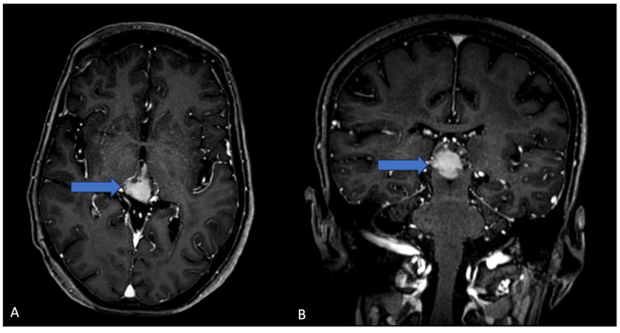

Behind the Pineal Gland: A Case Report on Pineoblastoma in a Teenager

Soumia Kriouile*, Yassine Zerhari, Soukayna Jabour, Omar El Aoufir and Laila Jroundi. 16(12): 01-05.